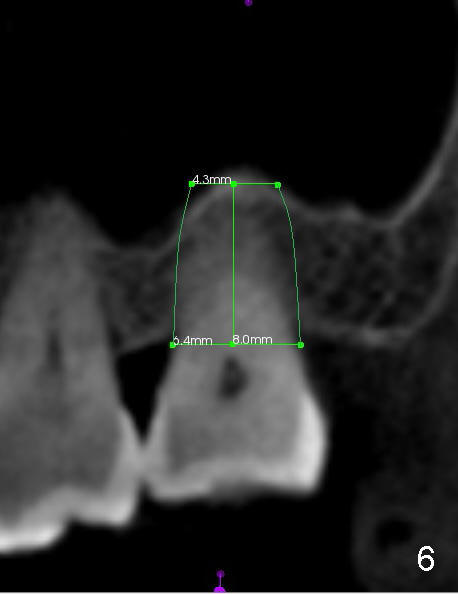

When the buccal roots are fused, there are 3 potential sites for immediate implant (Fig.1'): septum (*), buccal (B) and palatal (P) sockets. Septal placement (6.9x8 mm bone level implant) is the most ideal for restoration (Fig.3). The length of the implant can be increased (10 mm) with sinus lift so that the base of the implant between the buccal and palatal apices in height (Fig.4). Primary stability is derived mainly from the implant body engagement into the septum (Fig.5 coronal section through the septum). If bone density in the septum is high, a small implant may be appropriate (Fig.6,7: 6.4x8 mm). The large implant (6.9 mm) is chosen so that amount of bone graft to be used (Fig.8 red circles) is less.